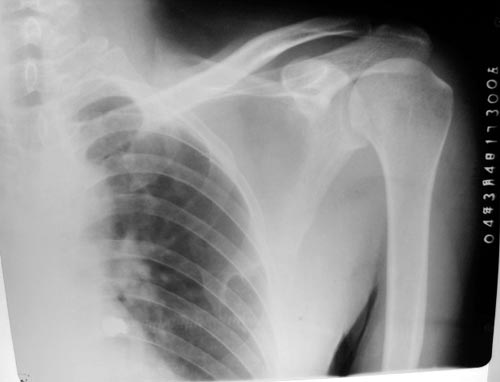

以下是引用lkc8963在2006-3-20 0:01:00的发言:[br]骨软骨瘤基本可定,至于有没有恶性变,本例依据不足,似见软块但皮下脂肪尚清,不知临床表现倒底有没有肿块还是突起?建议ct或穿刺检查。